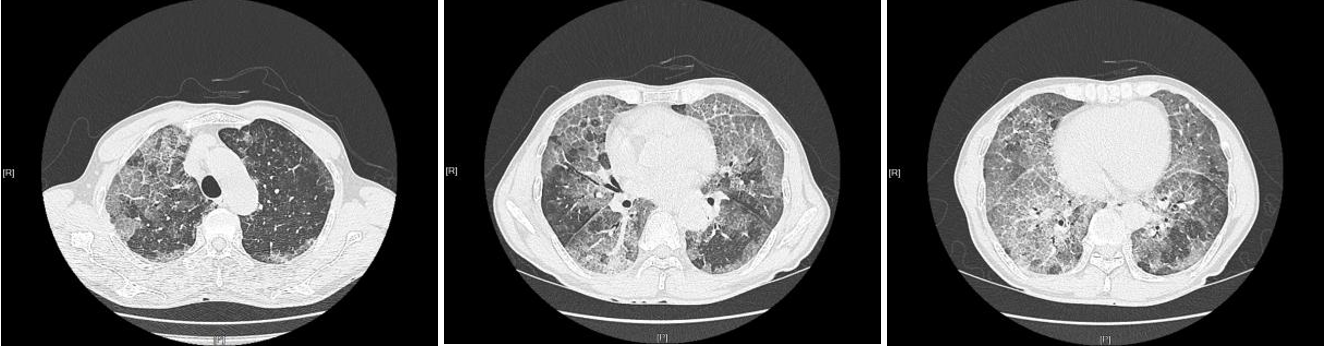

治疗后两肺渗出阴影明显吸收